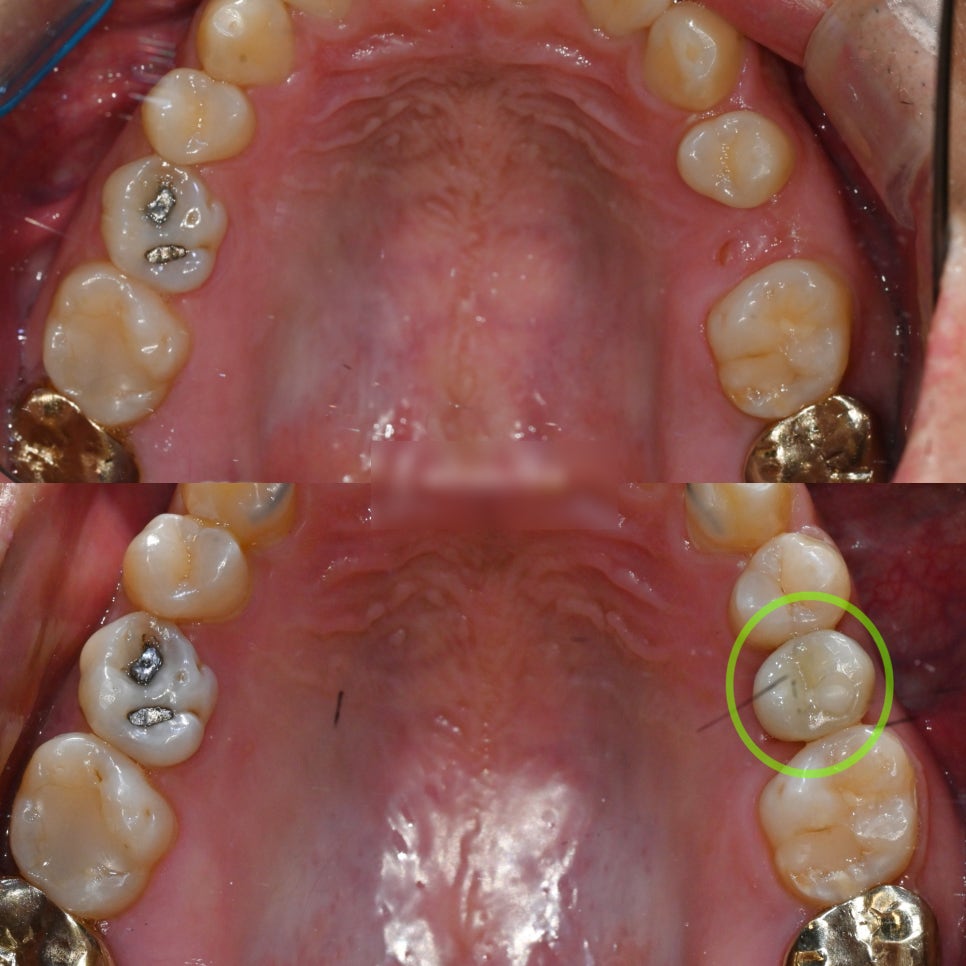

『치료 후』

부분교정과 임플란트 수술을 마친 후 모습입니다.

치아를 이동시켜 공간을 만드는

부분교정은 비교적 빠르게 마무리되었습니다.

그와 동시에 앞니도 가지런히 배열 완료되었습니다.

처음엔 좁았던 발치 공간이

제대로 확보되면서

지르코니아 보철(크라운)이 계획대로

예쁘게 잘 들어간 모습입니다.